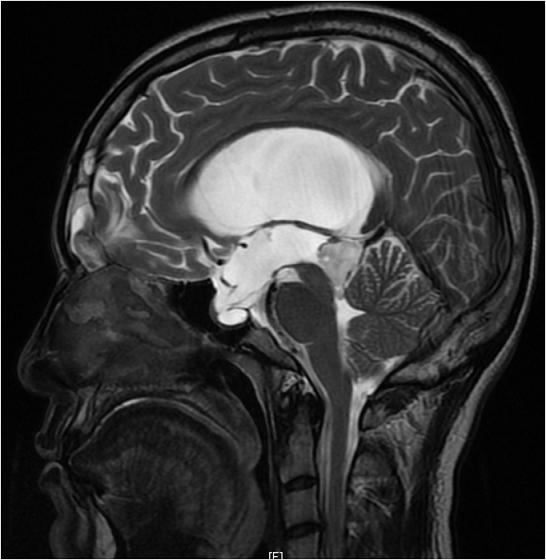

Une brèche ostéo-durale post-traumatique peut se révéler de façon tardive, à l'occasion d'une augmentation de la pression intracrânienne. La majorité des rhinorrhées cérébrospinales post traumatiques s'estompent spontanément. La cicatrisation méningée peut être imparfaite. Une hyperpression du Liquide céphalorachidien à son contact peut faire reparaitre la rhinorrhée. De ce fait, toute fuite post traumatique tardive de liquide céphalo-rachidien doit faire rechercher des facteurs de risque d'hypertension intracrânienne. Le traitement est alors chirurgical pour prévenir le risque de méningite. Un homme âgé de 26 ans, aux antécédents de traumatisme crânien avec perte de connaissance initiale il y a 3 ans (TDM cérébrale initiale sans anomalies), a consulté pour une rhinorrhée claire unilatérale droite évoluant depuis 06 mois, récidivante et aggravée par la position proclive. L'examen physique a révélé une rhinorrhée claire droite d'aspect eau de roche et de faible abondance sans notion de fièvre ni de syndrome méningé. L'examen neurologique était normal. L'étude du liquide de rhinorrhée a conclut au liquide céphalo-rachidien. L'IRM cérébrale a objectivé une méningo-encéphalocèle frontale droite, un processus intra-ventriculaire du troisième ventricule de 23 x 20 x 24cm avec hydrocéphalie en amont non active évoquant une tumeur gliale de bas grade. La TDM du massif facial a révélé une brèche osseuse de 1 cm du toit du sinus frontal droit avec présence de méningocèle. Le patient a été opéré en neurochirurgie par ventriculocisternestomie endoscopique et a bénéficié d'une réfection de la brèche ostéo-durale par volet frontal. Les suites opératoires étaient simples.